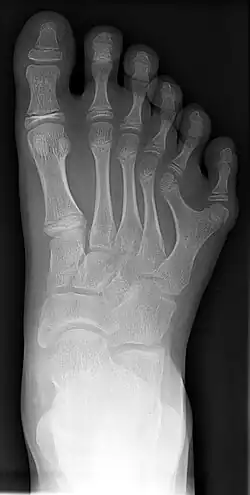

A polidactilia ou polidatilia (do grego πολύς, "muitos" e δάκτυλος "dedo") é uma anomalia causada pela manifestação de um alelo autossômico variável,dominante com expressividade consistindo na alteração quantitativa anormal dos dedos da mão (quirodáctilos) ou dos dedos do pé (pododáctilos).

Há uma variação muito grande na expressão dessa característica, desde a presença de um dedo extra, completamente desenvolvido, até a de uma simples profusão carnosa.